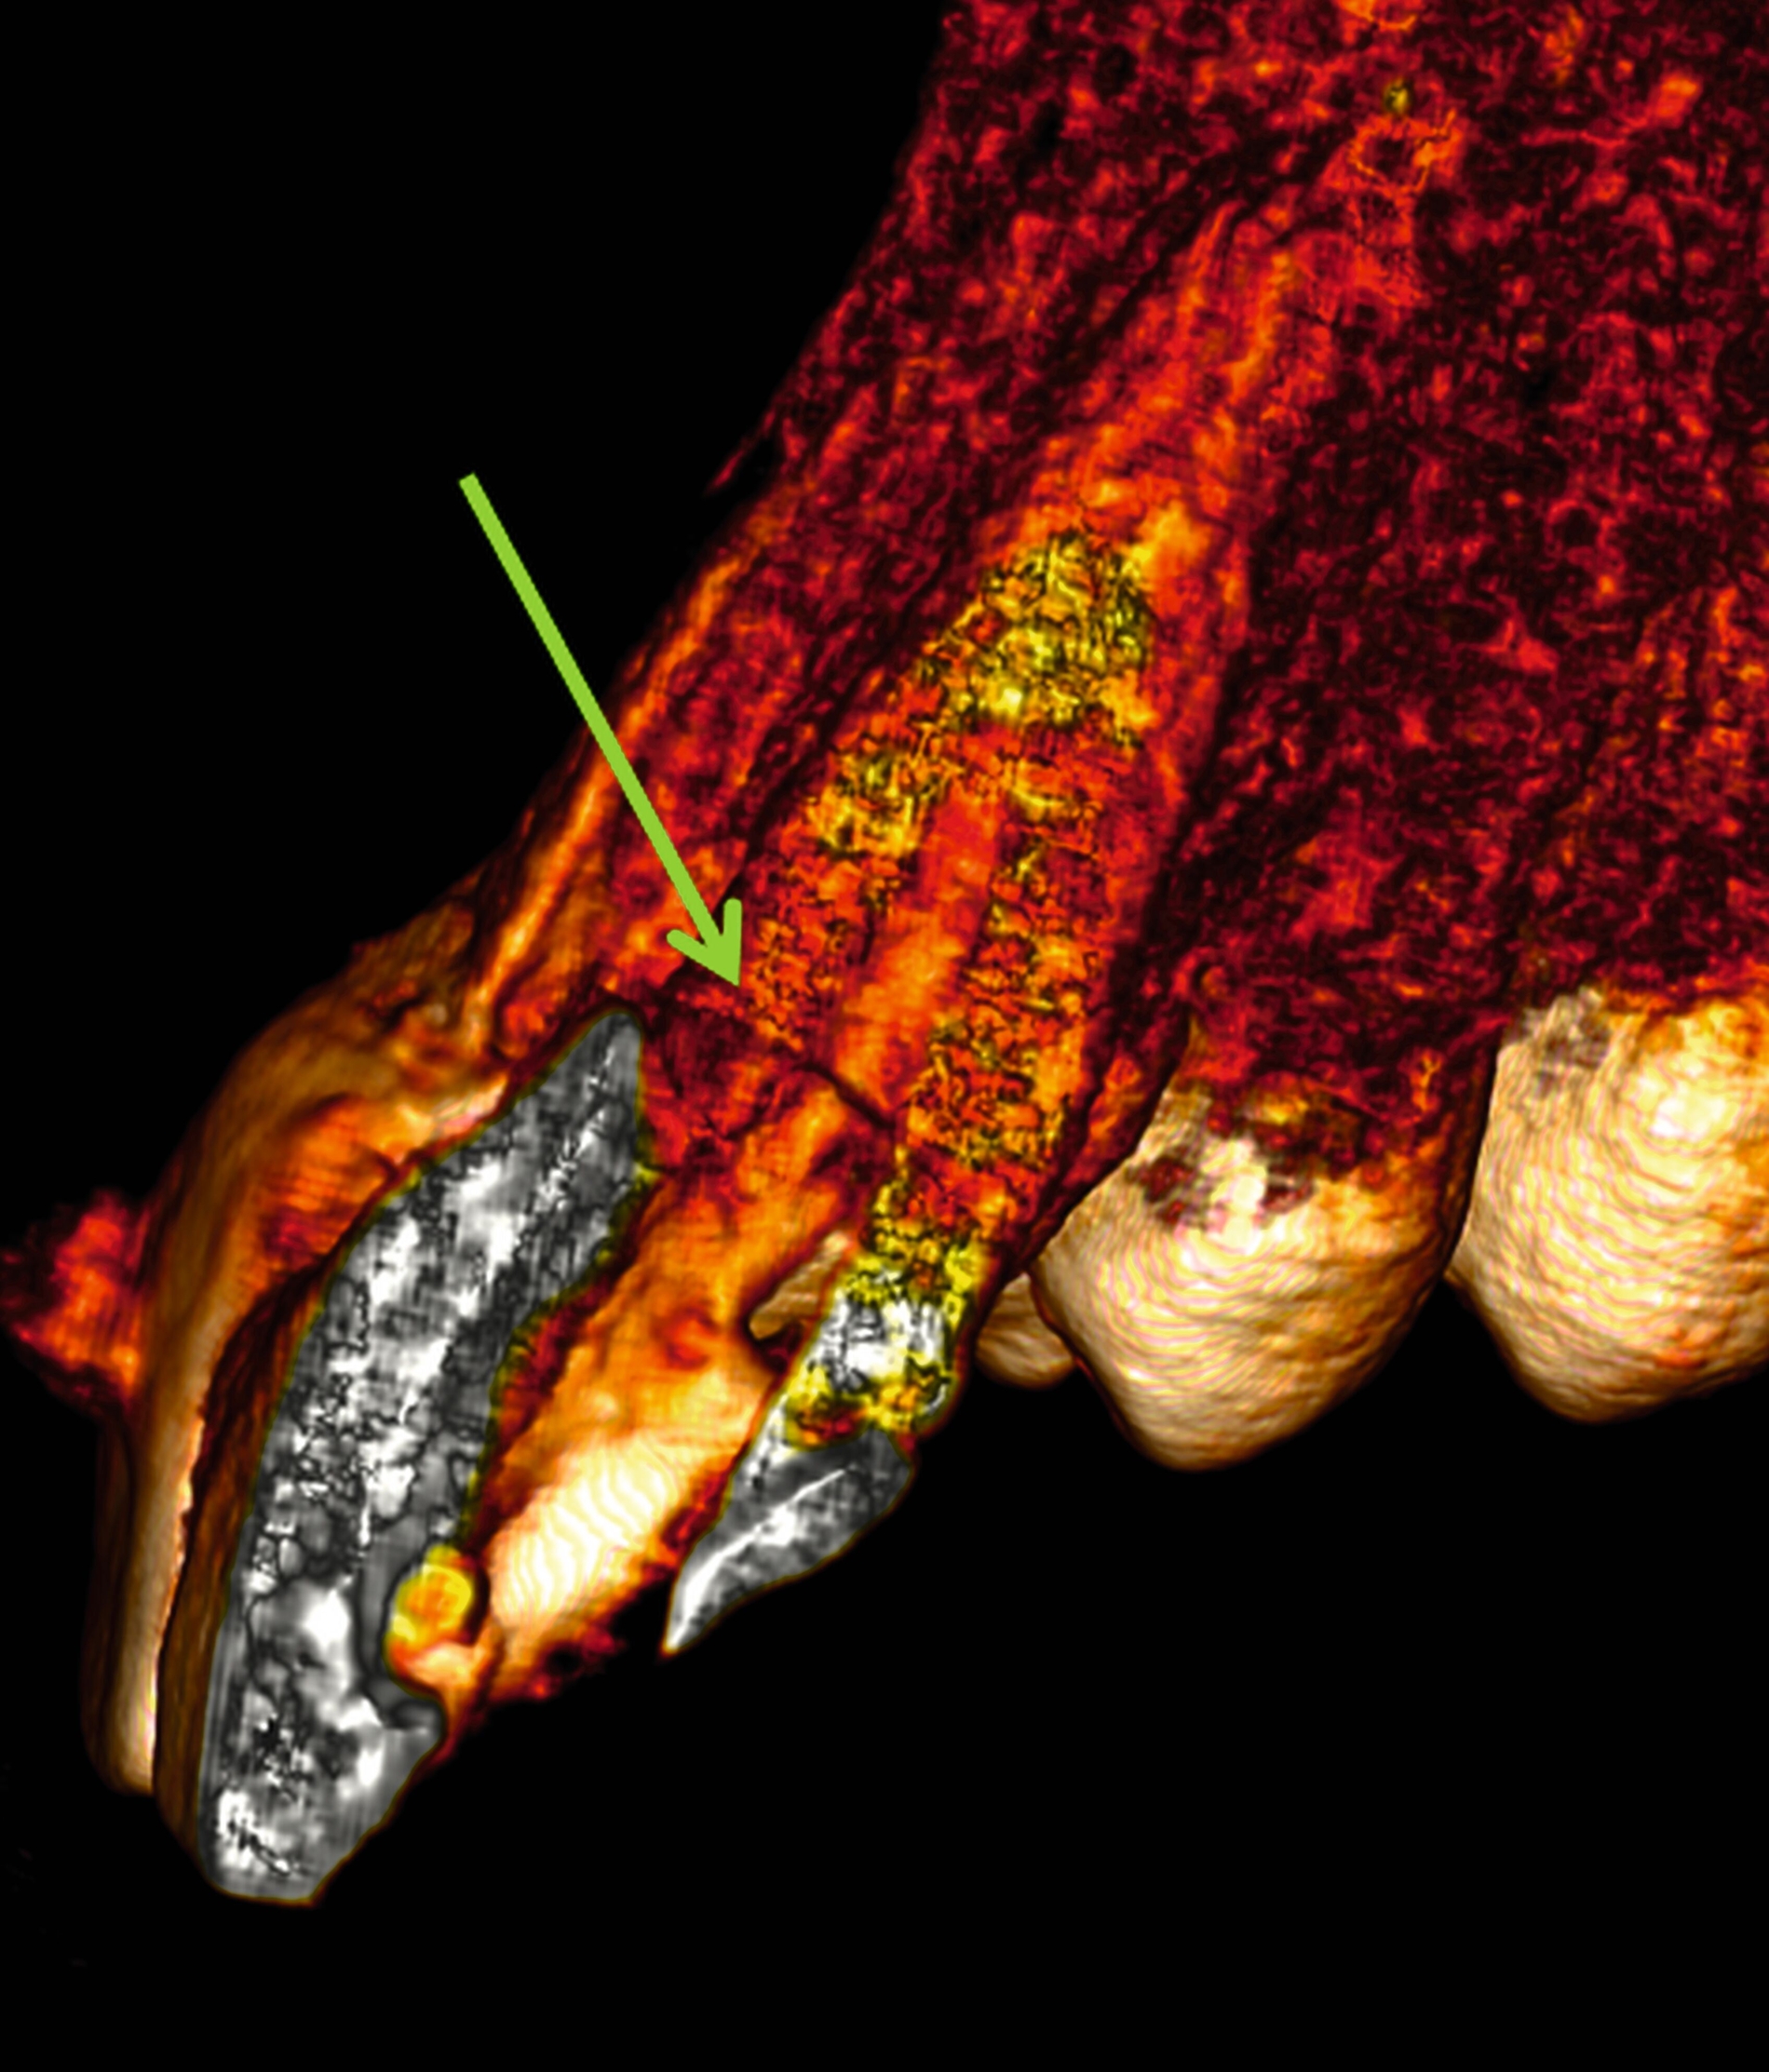

Im Hinblick auf Kronen-Wurzel-Frakturen beziehungsweise zervikale Wurzelfrakturen stellt die kieferorthopädische Extrusion eine schonende Behandlung von Vorteil dar, da bei schneller Extrusion die Gingivahöhe erhalten bleibt. Prapas et al. unterscheiden hierbei die klassische langsame kieferorthopädische Extrusion (maximal 1-2 mm pro Monat) durch leichte Kräfte und die schnelle Extrusion, bei der der Zahn mit starken Kräften aus der Alveole bewegt wird (3-4 mm pro Monat) [Prapas et al., 2008]. Während bei der langsamen Extrusion Alveolarknochen und Weichgewebe dem Zahn in gleichem Ausmaß zu folgen scheinen, bleiben bei der schnellen Extrusion die umgebenden Gewebe weitgehend zurück [Prapas et al., 2008].

Um bei einer schnellen kieferorthopädischen Extrusion sicherzustellen, dass keine limbale Knochenapposition durch eine Mitwanderung der Gingiva erfolgt, sollte dabei in regelmäßigen Abständen eine suprakrestale Fibrotomie durchgeführt werden [Carvalho et al., 2006]. Wird bei der kieferorthopädischen Extrusion keine regelmäßige suprakrestale Fibrotomie durchgeführt, kommt es auch zu einer Koronalverlagerung von Gingiva und Knochen. Dies ist bei einer nachfolgend angestrebten restaurativen Versorgung, die die Frakturränder in der Restauration fassen soll, in der Regel nicht erwünscht [Carvalho et al., 2006].

Langsame kieferorthopädische Extrusionen mit moderaten kieferorthopädischen Kräften ohne suprakrestale Fibrotomien hingegen können indiziert sein, wenn Gewebe aufgebaut werden soll oder Gingivaverläufe kieferorthopädisch korrigiert werden sollen [Prapas et al., 2008; Bauer et al., 2022].

Eine Sonderform der kieferorthopädischen Extrusion ist die kieferorthopädische Extraktion, bei der die gesamte Wurzel langsam und kontrolliert aus der Alveole gehoben und am Ende extrahiert wird. Dieses Verfahren wird insbesondere dann angewendet, wenn ein Implantatbett mit ausreichendem Knochenangebot geschaffen werden soll [Bauer et al., 2019]. Schnelle und langsame Extrusionstechniken können jedoch auch bei einem Patienten kombiniert werden, wenn sowohl Anpassungen des Gingivaverlaufs als auch Veränderungen der Stumpfhöhe zur nachfolgenden Restauration geplant sind (Abbildung 2).